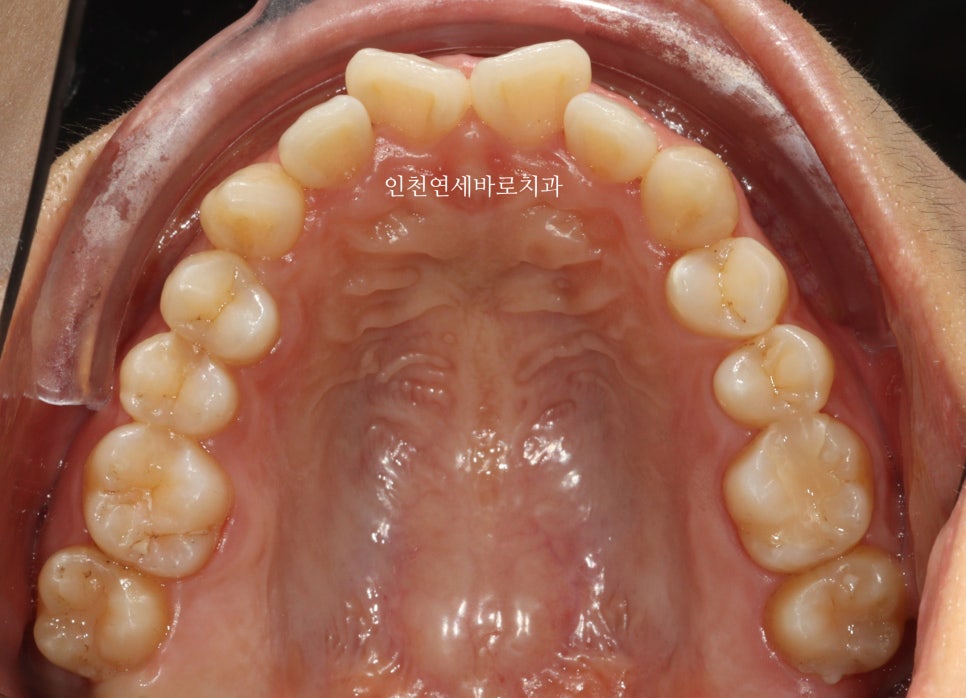

치료 전후 비교

전후 비교입니다

전 후 교합의 비교입니다.

안정적으로 교합이 형성되었습니다